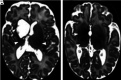

Fig 4.

Germinal matrix. T1- (A) and T2-weighted images (B) of an infant born at 24 + 2 weeks and imaged at 26 + 7 weeks, demonstrating normal appearance of the germinal matrix for this gestation, here seen as a thin rim of low-T2/high-T1 signal in the subependymal region (arrows, A and B). Germinal matrix hemorrhage is a complication of prematurity and is distinguished from normal matrix remnants by its shape and size. C, An infant born at 26 + 6 weeks and imaged at 42 + 3 weeks. D, An infant born at 28 weeks and imaged at 44 + 5 weeks. The germinal matrix hemorrhage is recognized here as a thin, irregular focus of T2 low signal isolated to the subependyma, which may be unilateral (arrows, C and D).